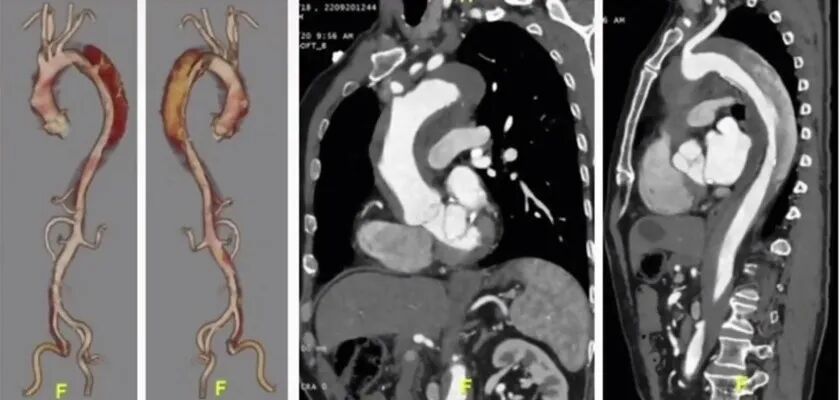

急诊CTA:可见主动脉夹层(A型),累及弓上分支动脉。主动脉自升主动脉起,全程壁间血肿。腹腔干、肠系膜上动脉及左肾动脉真腔显影。

支架植入后:术后12个月随访:复查主动脉CTA可见主动脉重塑良好,弓上三分支显影通畅,无内漏形成。